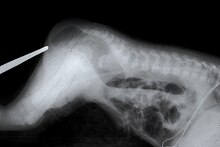

В диагностике атрезии хоан также применяют контрастное рентгенологическое исследование. Оно заключается в выполнении рентгенографии черепа в боковой проекции после введения в полость носа рентгенконтрастного раствора. Скопление контраста в носовой полости и отсутствие его прохождения в носоглотку подтверждает диагноз атрезии хоан. При частичной атрезии на рентгенограмме можно наблюдать частичное прохождение контраста в глотку в виде узких полос.